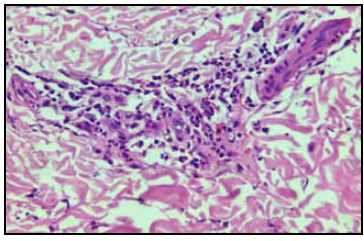

Dadas las características clínicas, su grupo etario y los resultados obtenidos en los paraclínicos, se solicitó valoración por oftalmología quienes sugerían neuropatía de ojo izquierdo, y se descartó polimiositis como causalidad, al no cumplir los criterios de Bohan y Peter (no presentaba lesiones cutáneas, mejoría clínica al administrar esteroides, enzimas musculares normales y ausencia de un patrón miopático en EMG), sugiriendo una neuropatía de pequeñas fibras, por lo que se inició manejo adicional con pregabalina y se realizó biopsia vascular y muscular (Figuras 1y2), con la cual se confirmó el diagnóstico de poliarteritis nodosa (PAN) al encontrarse un infiltrado inflamatorio mixto de predominio polimorfonuclear, linfocitos e histiocitos, y cumplía cinco de los 10 criterios de la ACR para PAN. Ante estos resultados se decidió iniciar manejo con ciclofosfamida (seis ciclos de 1 gr diluidos en 250 cc de SSN), prednisona oral 1 mg/Kg/día, azatriopina oral (50 mg c/12 h), ácido fólico (1 mg/día), con lo que se observó una evolución favorable y se lograron objetivos con el tratamiento instaurado, se dio salida de la institución con orden para volver mensualmente a sus ciclos de ciclofosfamida.

Figura 2 Biopsia muscular . Estroma con arterias de paredes delgadas, con infiltrado inflamatorio mixto de predominio polimorfonuclear, linfocitos e histiocitos.

Al realizar la biopsia se prefiere el abordaje menos agresivo (biopsia de piel o músculo), puesto que al tomar la muestra de órganos como el riñón o hígado se corre el riesgo de hemorragia 10. Generalmente se hallan infiltrados de linfocitos, macrófagos, neutrófilos, un número variable de eosinófilos, y en casos de lesiones activas se observa necrosis fibrinoide. En estados más avanzados, la formación de nuevos vasos se vuelve aparente. En lesiones avanzadas, la remodelación vascular conlleva al desarrollo de hiperplasia de la túnica íntima y cambios fibróticos difusos en la pared del vaso. La lesión severa de la pared puede resultar en la formación de microaneurismas y la trombosis puede contribuir también a la oclusión vascular 11-13.